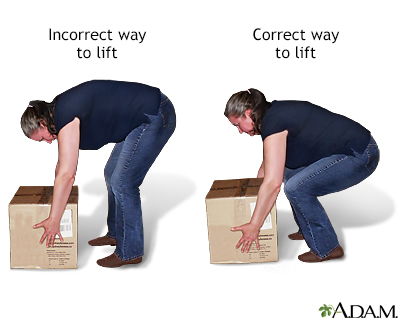

It is also very important to learn to lift and bend properly. Follow these tips:

- If an object is too heavy or awkward, get help.

- Spread your feet apart to give your body a wide base of support when lifting.

- Stand as close as possible to the object you are lifting.

- Bend at your knees, not at your waist.

- Tighten your stomach muscles as you lift the object or lower it down.

- Hold the object as close to your body as you can.

- Lift using your leg muscles.

- As you stand up with the object, do not bend forward.

- Do not twist while you are bending down for the object, lifting it up, or carrying it.